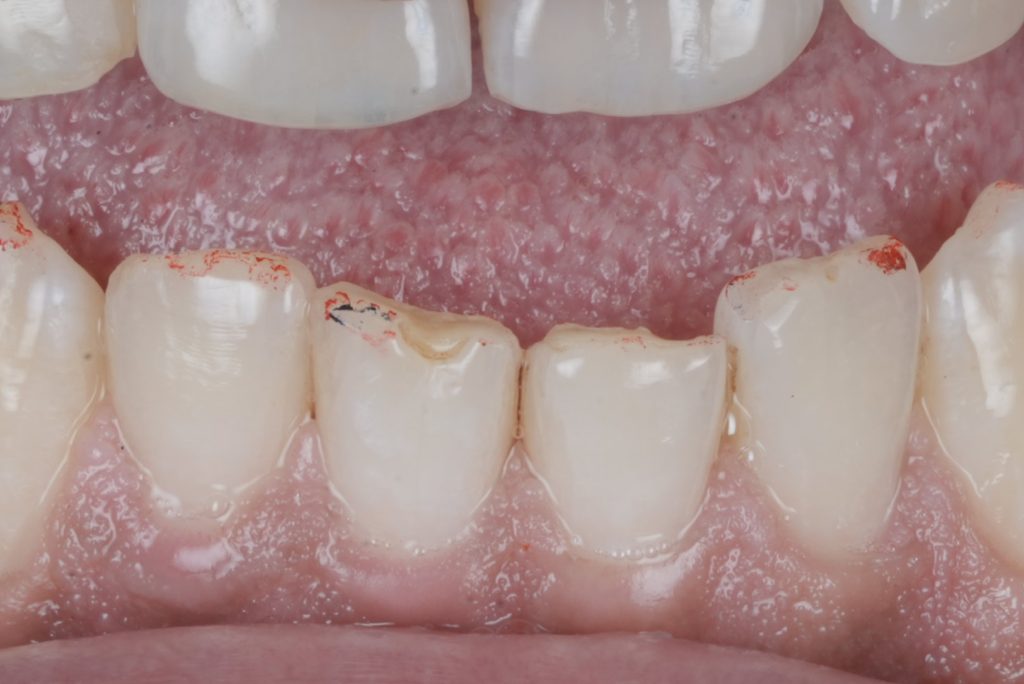

The patient presented with anterior teeth showing cervical wear, incisal edge defects, and discoloration. The esthetic concern was compounded by loss of natural morphology and translucency. The treatment plan focused on direct composite veneers to restore harmony, form, and function in a minimally invasive manner.

5. Finishing and Polishing

•Contours were refined with fine-grit diamond burs and finishing discs.

•Surface texture was recreated with microanatomical secondary grooves to mimic natural tooth morphology.

•Final gloss was achieved using silicone polishers and diamond paste lucida by style Italiano , reproducing enamel luster.

6. Final Outcome

•The veneers blended seamlessly with adjacent dentition in terms of shade, morphology, and translucency.

•The patient was satisfied with the natural esthetics, restored smile harmony, and minimal tooth reduction involved